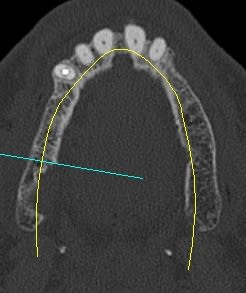

pour le sinus lift, une fois la membrane élevée à la hauteur que je me suis fixé (mon objectif est de mettre des implants de 10 mm) je dépose au contact de la membrane le contenu d'une seringue d'OSTEON lifting 0,25 cc

ses particules sont très fine cela me permet de protéger la membrane

puis dans ce cas 1cc d'osteon en pot de 1cc de granulomérie 0,5-1

comme tu pourra le constater on met peu d'os c'est sans doute lié à la présence des implants (qui ont un certain volume), au choix de la longueur.

en ce qui concerne la planification j'ai une 3D kodak je me sert des cotes de l'implant Alphatech qui bien que n'ayant pas la même forme, a les mêmes dimensions.